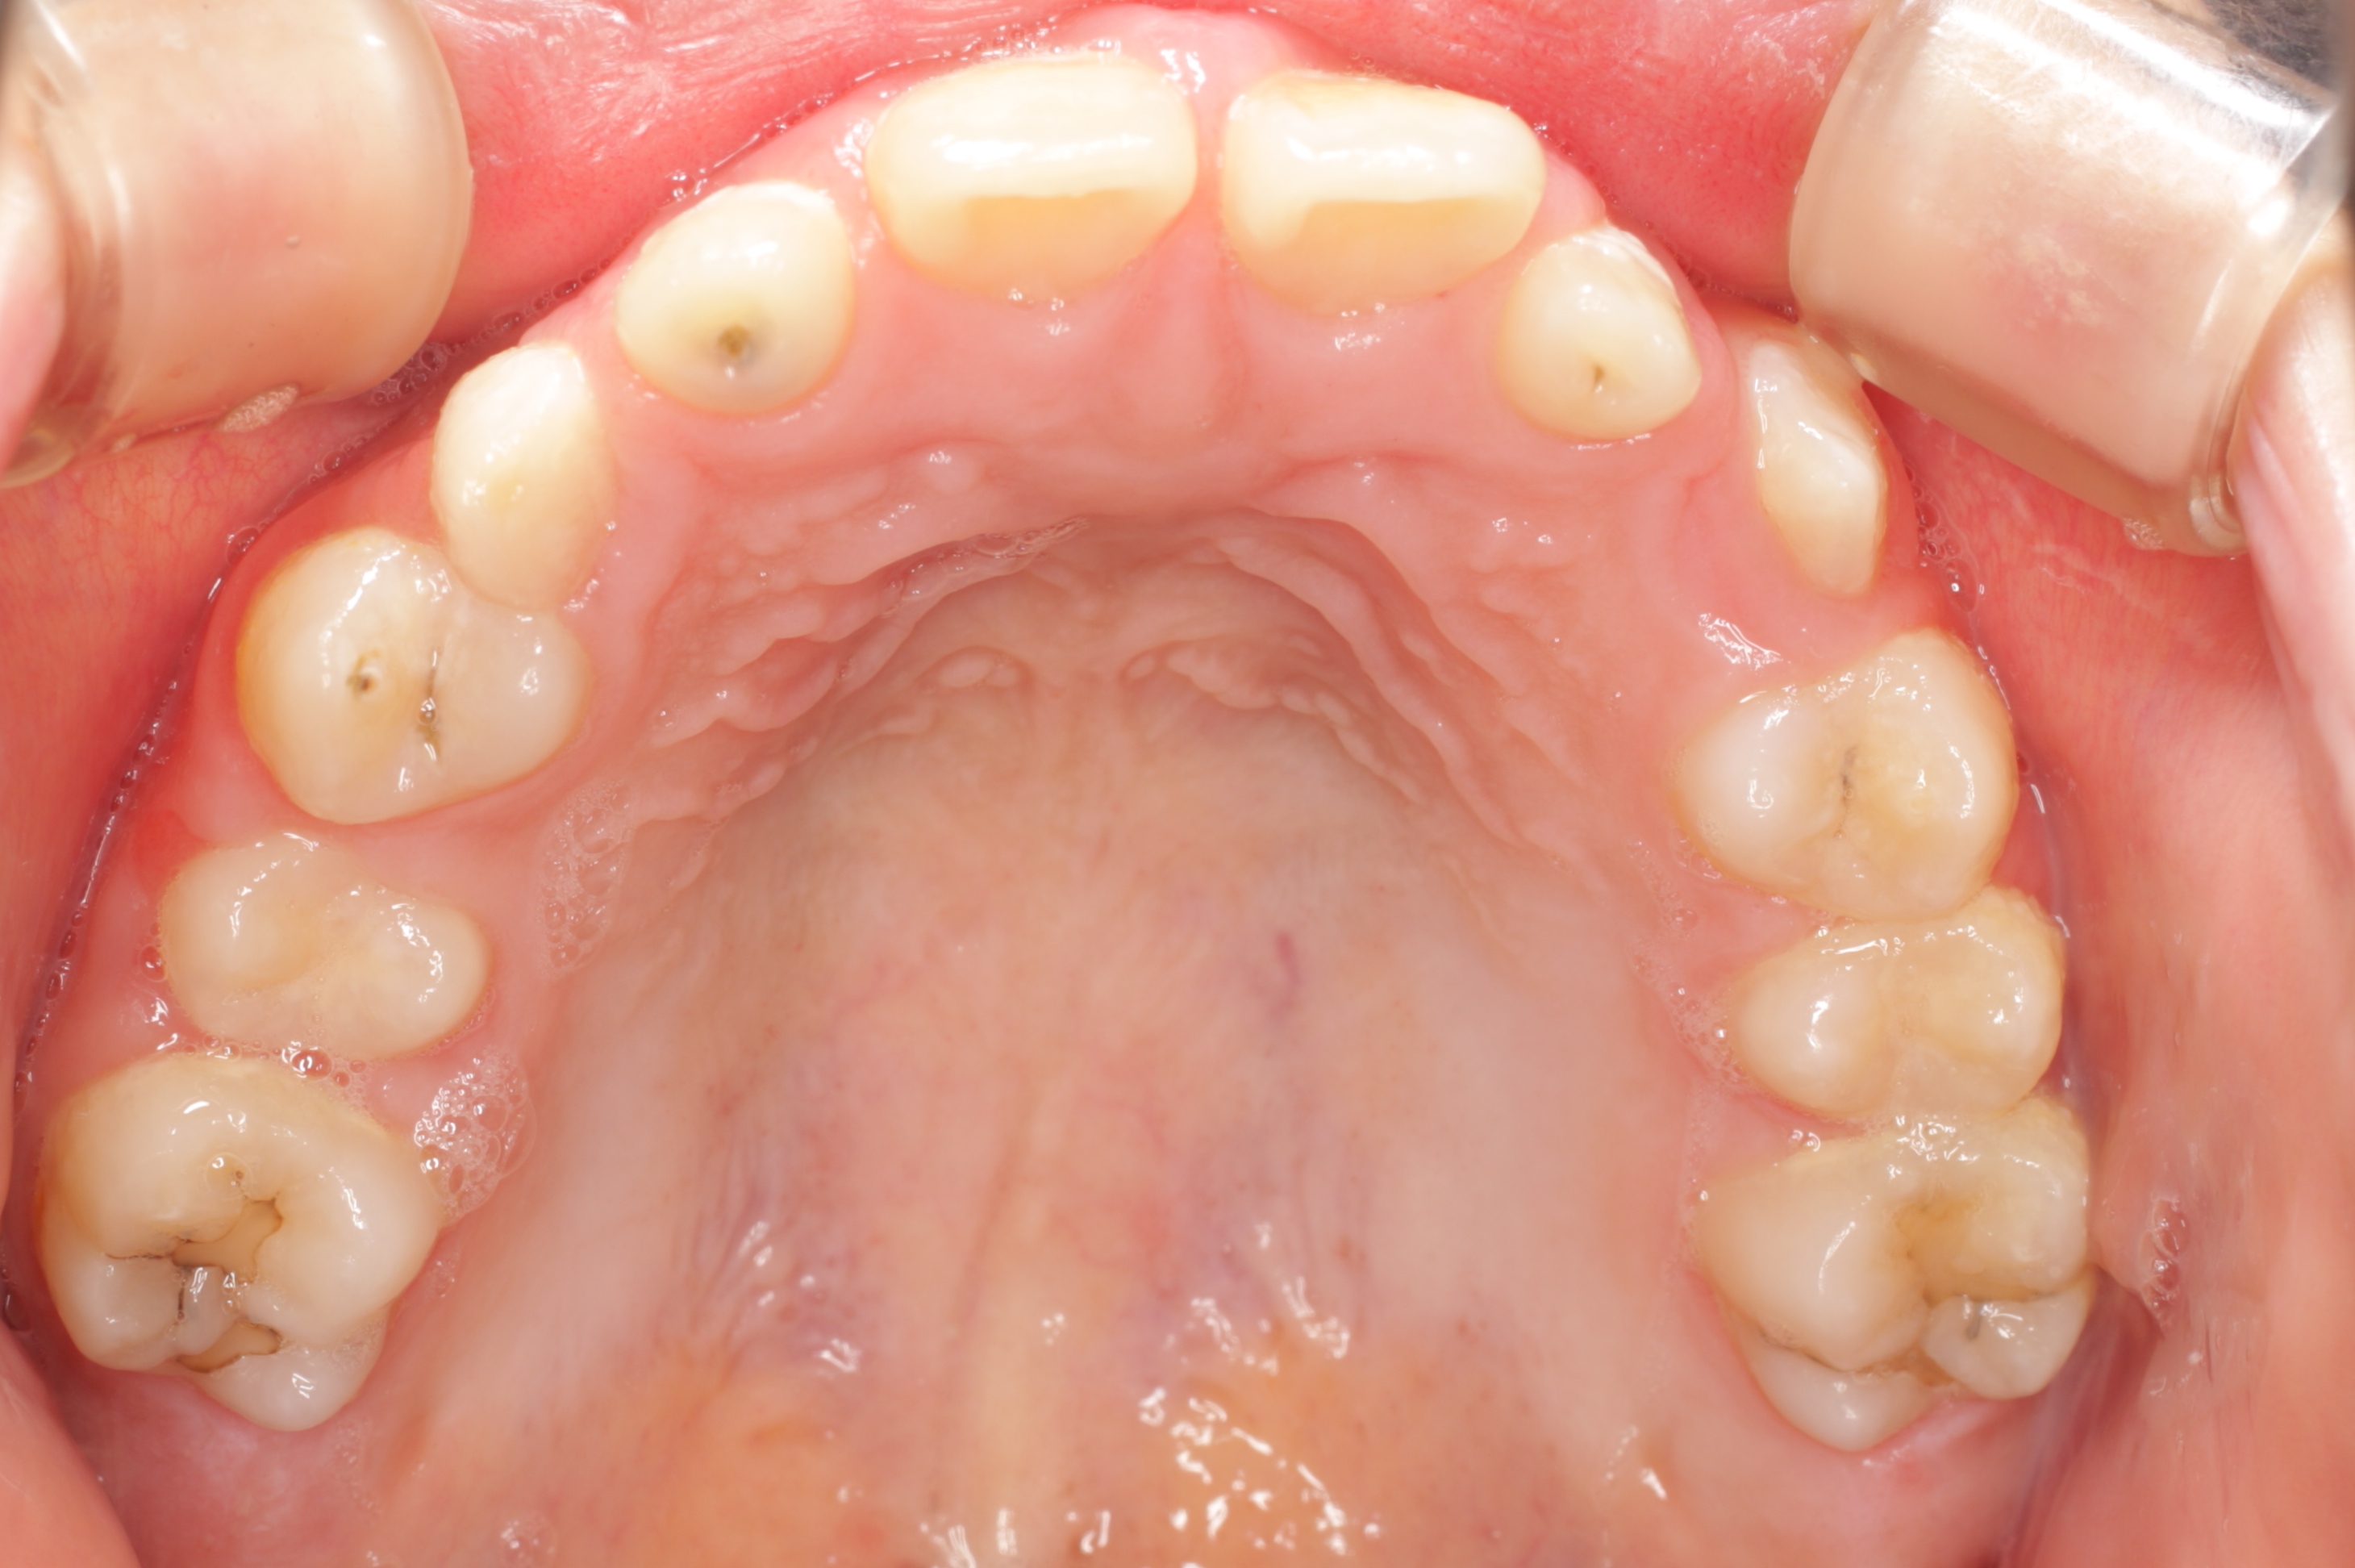

学校健診で虫歯と言われ、来院してくれた子供さんです。とても良い子で、お家の方も感じの良い方です。ただ、気がつくチャンスが無かっただけなのです。歯の大切さと予防歯科の重要性に。

歯科医や学校がもっと予防歯科の普及に頑張らないといけないなと深く反省させられる瞬間です。ごめんなさい。ごめんなさい。

一般的には「何本か虫歯があるので、歯医者に行ってなおしてもらおう」といった感覚なのでしょう。悲しいかな日本ではそれがフツーです。

問題はこの子の家庭に予防歯科の概念と知識が欠如している事なのです。何回も言っているように歯医者に行っても歯は元通りにはなりませんし、修繕が追いつかない程の速度で虫歯ができています。

この子は、これから一生の間に少なくとも100回は歯ぐきに注射をされて、少なくとも300回は通院し、歯を削られたり、神経を抜かれたり、銀歯を入れられたり、そしていつかは歯を抜かれたりするようになります。歯科医師の私にはこの悲しい将来が見えてしまいます。

一日も早く、一人でも多くの方が予防歯科の重要性に気がついて欲しいと思います。そのために私達歯科医療従事者も頑張ります!